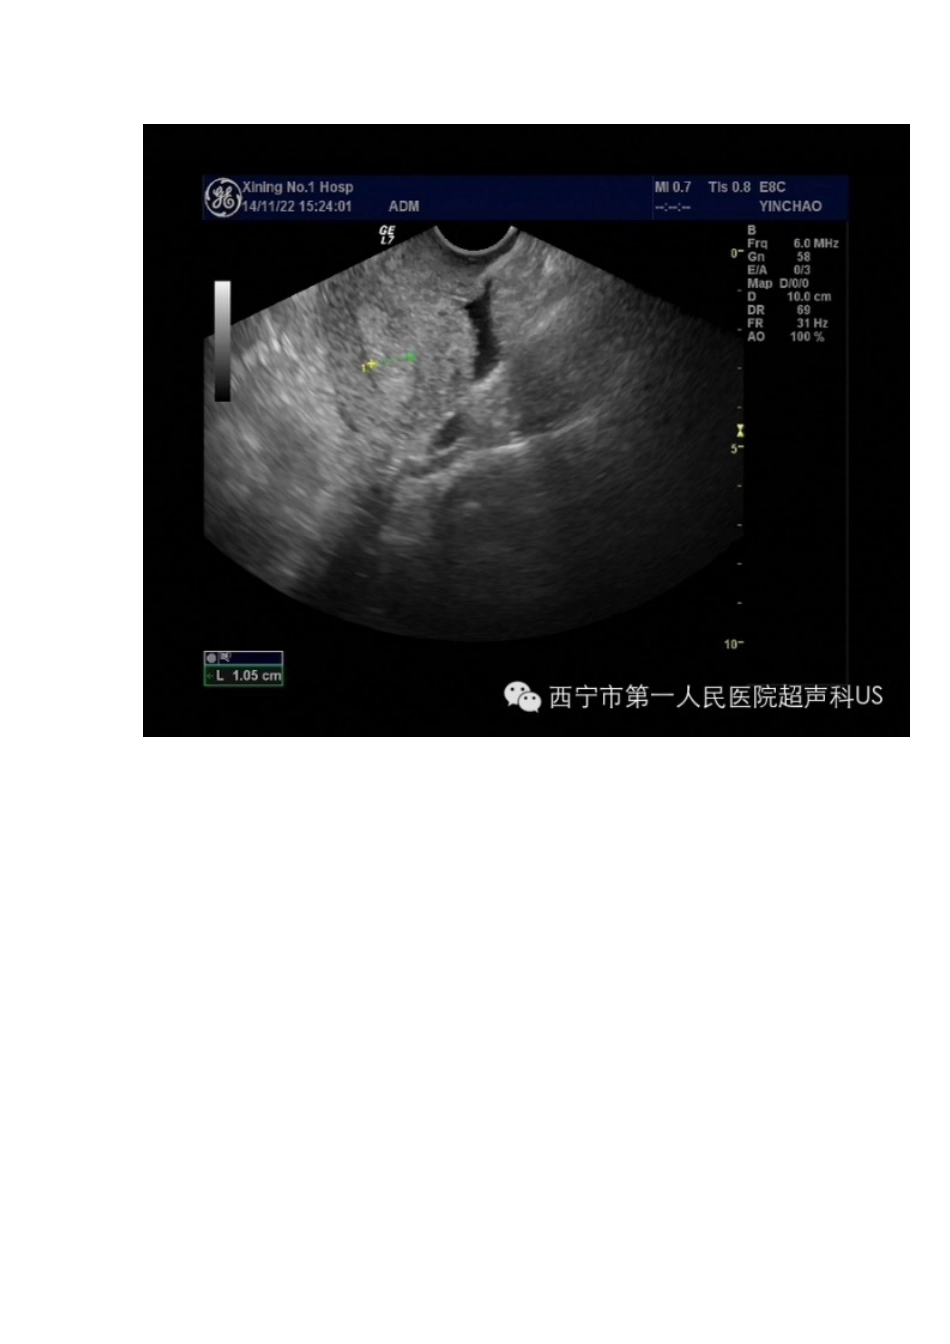

多囊卵巢(PCO)是超声做出的诊断,而多囊卵巢综合征(Pcos)的诊断是超声下的表现与高雄激素血症的临床症状结合得出的,比如月经稀发、多毛、痤疮、脂溢和肥胖。单凭超声图像不能确诊。PCOS通常采用2003年在鹿特丹召开的ESHREASRMPCO研讨会上通过的的定义,以下三种表现中如果出现两个:形态学、雄激素过高的临床或生化表现、月经稀发或闭经,即可诊断Pcos。病例一多囊卵巢综合征(pcos)超声表现有以下特征:(1)双侧卵巢增大,可为正常的2-3倍,主要是厚度增加,最大径线可达50mm。(2)卵泡包膜增厚,声像图显示卵巢轮廓清晰,表面回声增强,周围可出现一薄强回声环。(3)经阴道超声卵巢内可见到≥12个卵泡(经腹≥10个卵泡),直径在2-8mm。(4)髓质水肿,表现为卵巢中央髓质部见一强回声区。正常情况下声像图不显示卵巢髓质回声。(5)子宫正常大小或稍大。(6)长期无排卵或闭经时间较长者见宫腔内有强回声区,为增厚的子宫内膜。病例二病例三注:多卵泡卵巢(mfo):为青春期妇女的一种无排卵月经失调。超声表现为双侧卵巢偏大,内见多个小卵泡,直径约5mm,有时易与pcos混淆,但mfo与pcos有如下不同:①mfo卵巢虽偏大,但无饱满感;②无包膜增厚,表面回声不增强;③皮质层小卵泡较pcos之小卵泡稍大,而卵泡数目较pcos少;④无髓质水肿;⑤子宫通常偏小,显示子宫发育不良;⑥临床无多毛、肥胖等表现。有人认为mfo为一过渡阶段卵巢,可发展为正常卵巢,或成为pcos。